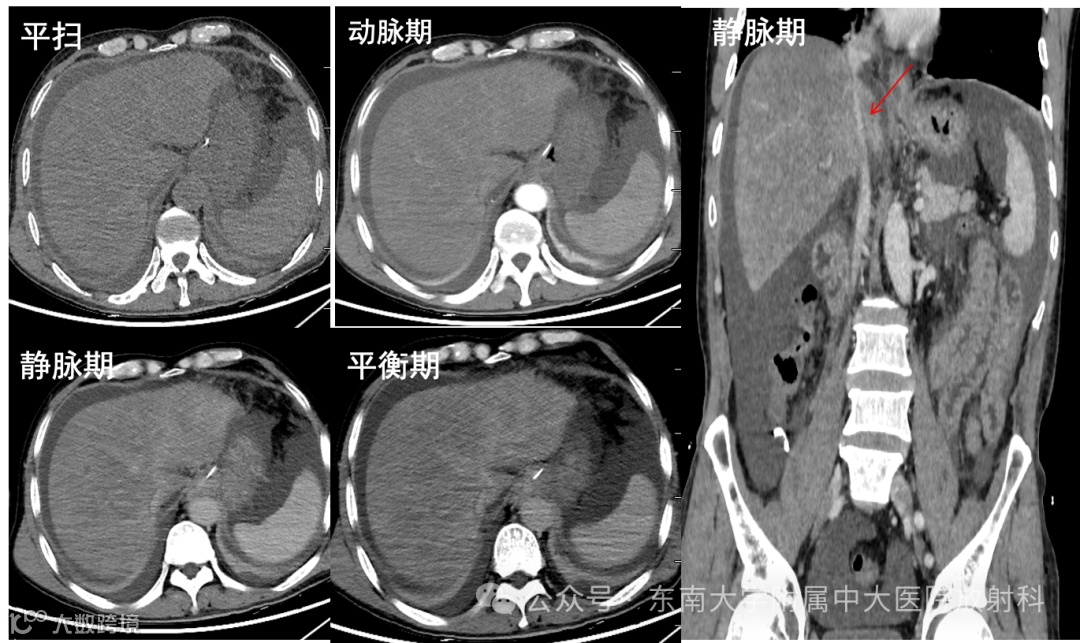

病例2

男性,66岁 -

主诉:腹胀伴双下肢水肿10余天 -

现病史:患者10 余天前服用自制“三七药酒”后感上腹胀痛,伴双下肢水肿,嗳气,大便发黑,伴胸闷,无呼吸困难,无腹痛腹泻,近期体重无变化,于当地医院就诊。否认“肝炎”病史。未予特殊治疗。现为进一步诊疗,来我院就诊,门诊以“肝功能异常”收住院。

影像学表现